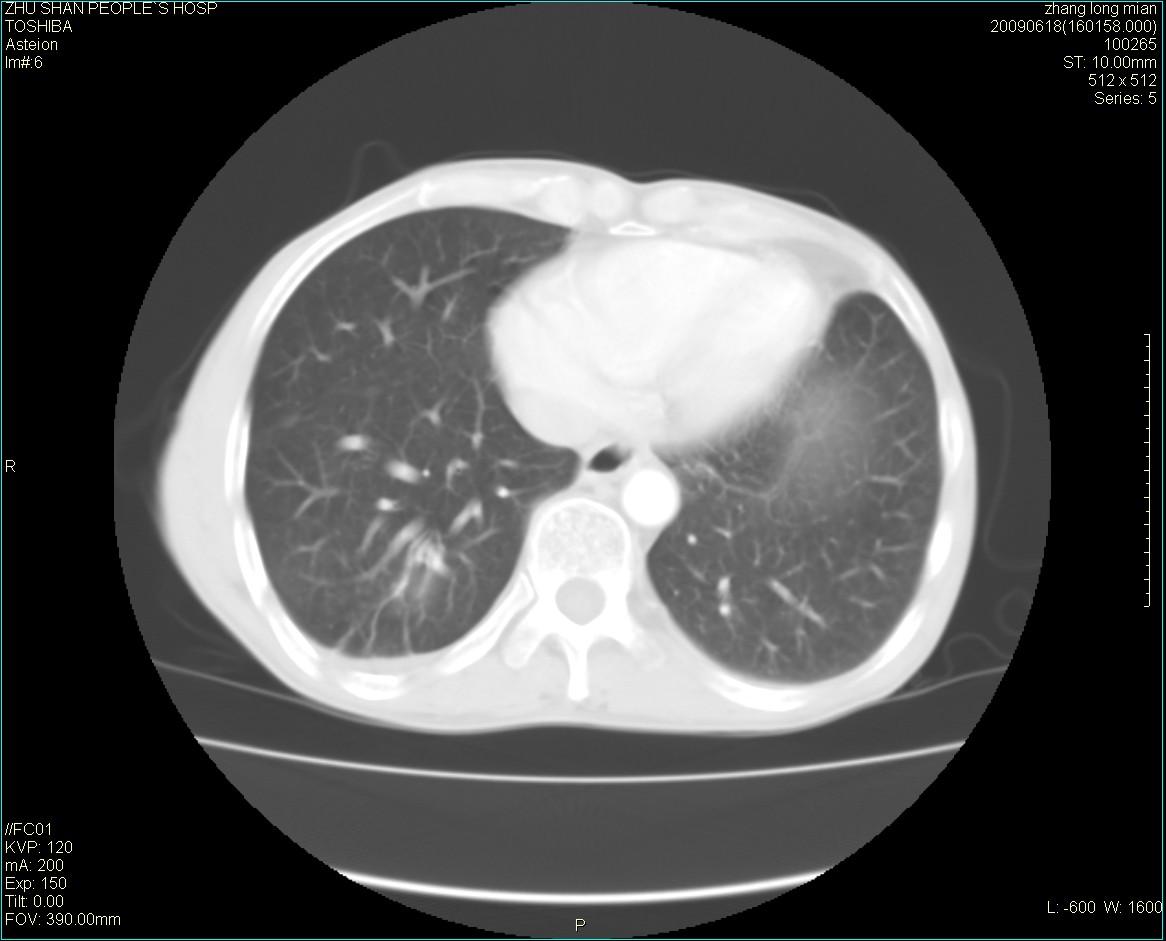

男性 65岁 胸片发现右下肺包块.诊断肺ca并纵隔转移没有问题吧!

两侧胸廓不对称,右侧呈塌陷改变,右肺萎缩。

右下肺见浅分叶状软组织块影,边缘有毛刺,其下部似见不完整偏心空洞影,邻近胸膜凹陷征,并胸腔积液。

增强见纵隔区气管隆突上下及左肺门区肿大淋巴结。左肺感染性病灶。

另见右上肺见一枚小结节影,性质待定。